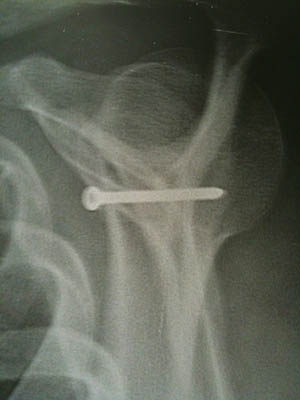

Elle consiste à prélever la partie antérieure de la coracoïde en gardant ses insertions musculaires coracobrachiales et de venir la visser à la partie antérieure et inférieure de la glène.

Pour aborder cette articulation, on incise horizontalement le sous scapulaire à son tiers moyen sur une largeur de 3 cm. L’articulation est exposée, la tête humérale réclinée par une lame malléable pour bien exposer le rebord antérieur de la glène. Le bourrelet glénoïdien est partiellement excisé pour accéder à l’os de la glène en avant. C’est dans cette zone antéro inférieure que sera vissée la butée osseuse. L’os glénoïdal sera bien avivé avant le vissage pour obtenir une fusion optimale ultérieure. La vis mesure en général 45 mm et est de diamètre 3,5 mm. On vérifie la bonne tenue de la butée qui doit affleurer la partie articulaire de la glène et doit la prolonger en avant.